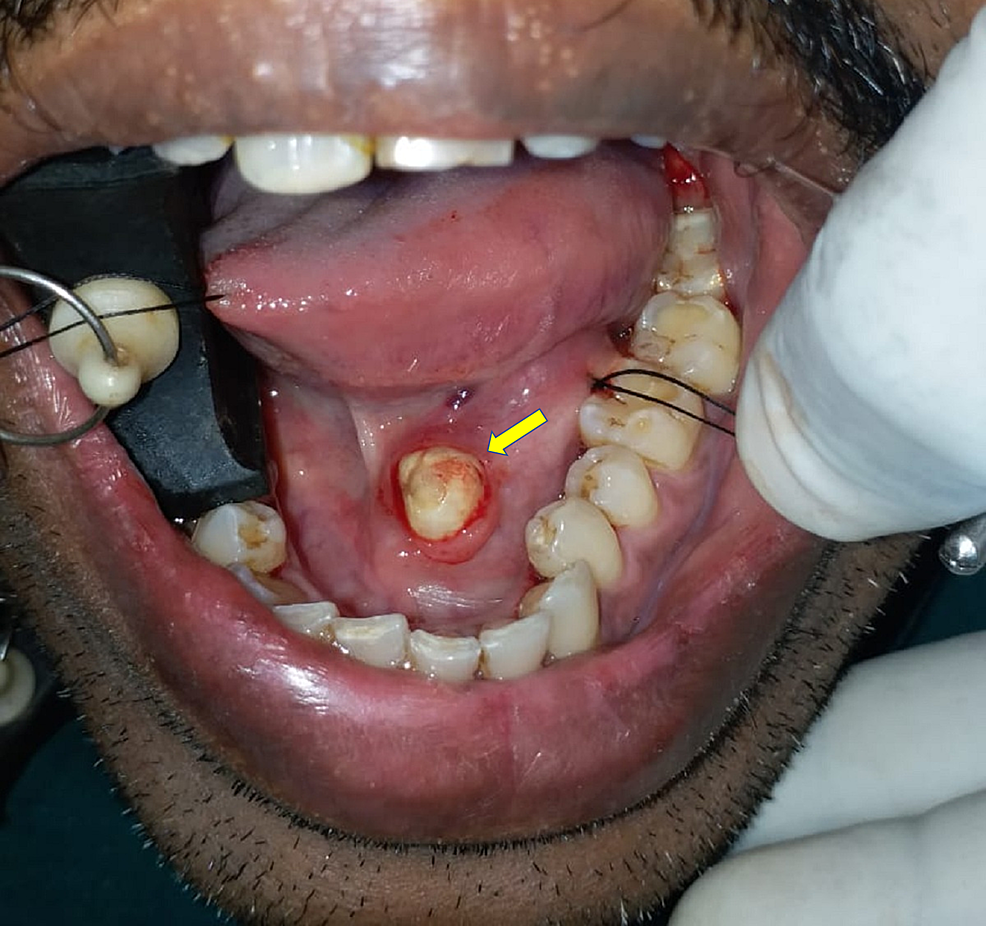

Sublingual Gland Stone Disease in Mouth Stock Image Image of closeup

Sublingual Gland Stone Disease in Mouth Stock Image Image of closeup What Is A Mouth Stone A stone can cause a blockage of the flow of spit (saliva), which can lead to pain and swelling of the affected salivary gland. Salivary stones, also called sialolithiasis, are hardened mineral deposits that form in the salivary glands. Salivary stones, also called sialoliths, are calcified organic masses that form within the salivary gland’s secretory system. Know more about its. What Is A Mouth Stone.